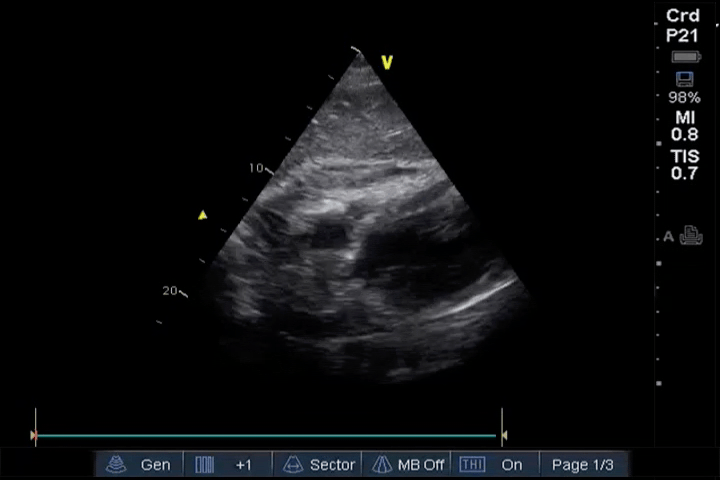

PLAX

PLAX view showing substantial pericardial effusion compromising left ventricular filling: This PLAX view demonstrates a substantial pericardial effusion that is compressing the left ventricle. The large fluid collection is limiting the filling of the left ventricle, which can lead to hemodynamic instability. This finding is concerning for tamponade and requires close monitoring and potential intervention.